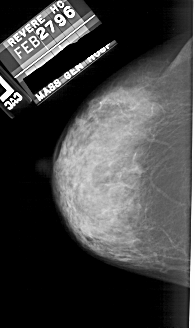

A_1753_1.RIGHT_MLO

RIGHT_MLO LINES 5491 PIXELS_PER_LINE 3136 BITS_PER_PIXEL 12 RESOLUTION 43.5 OVERLAY